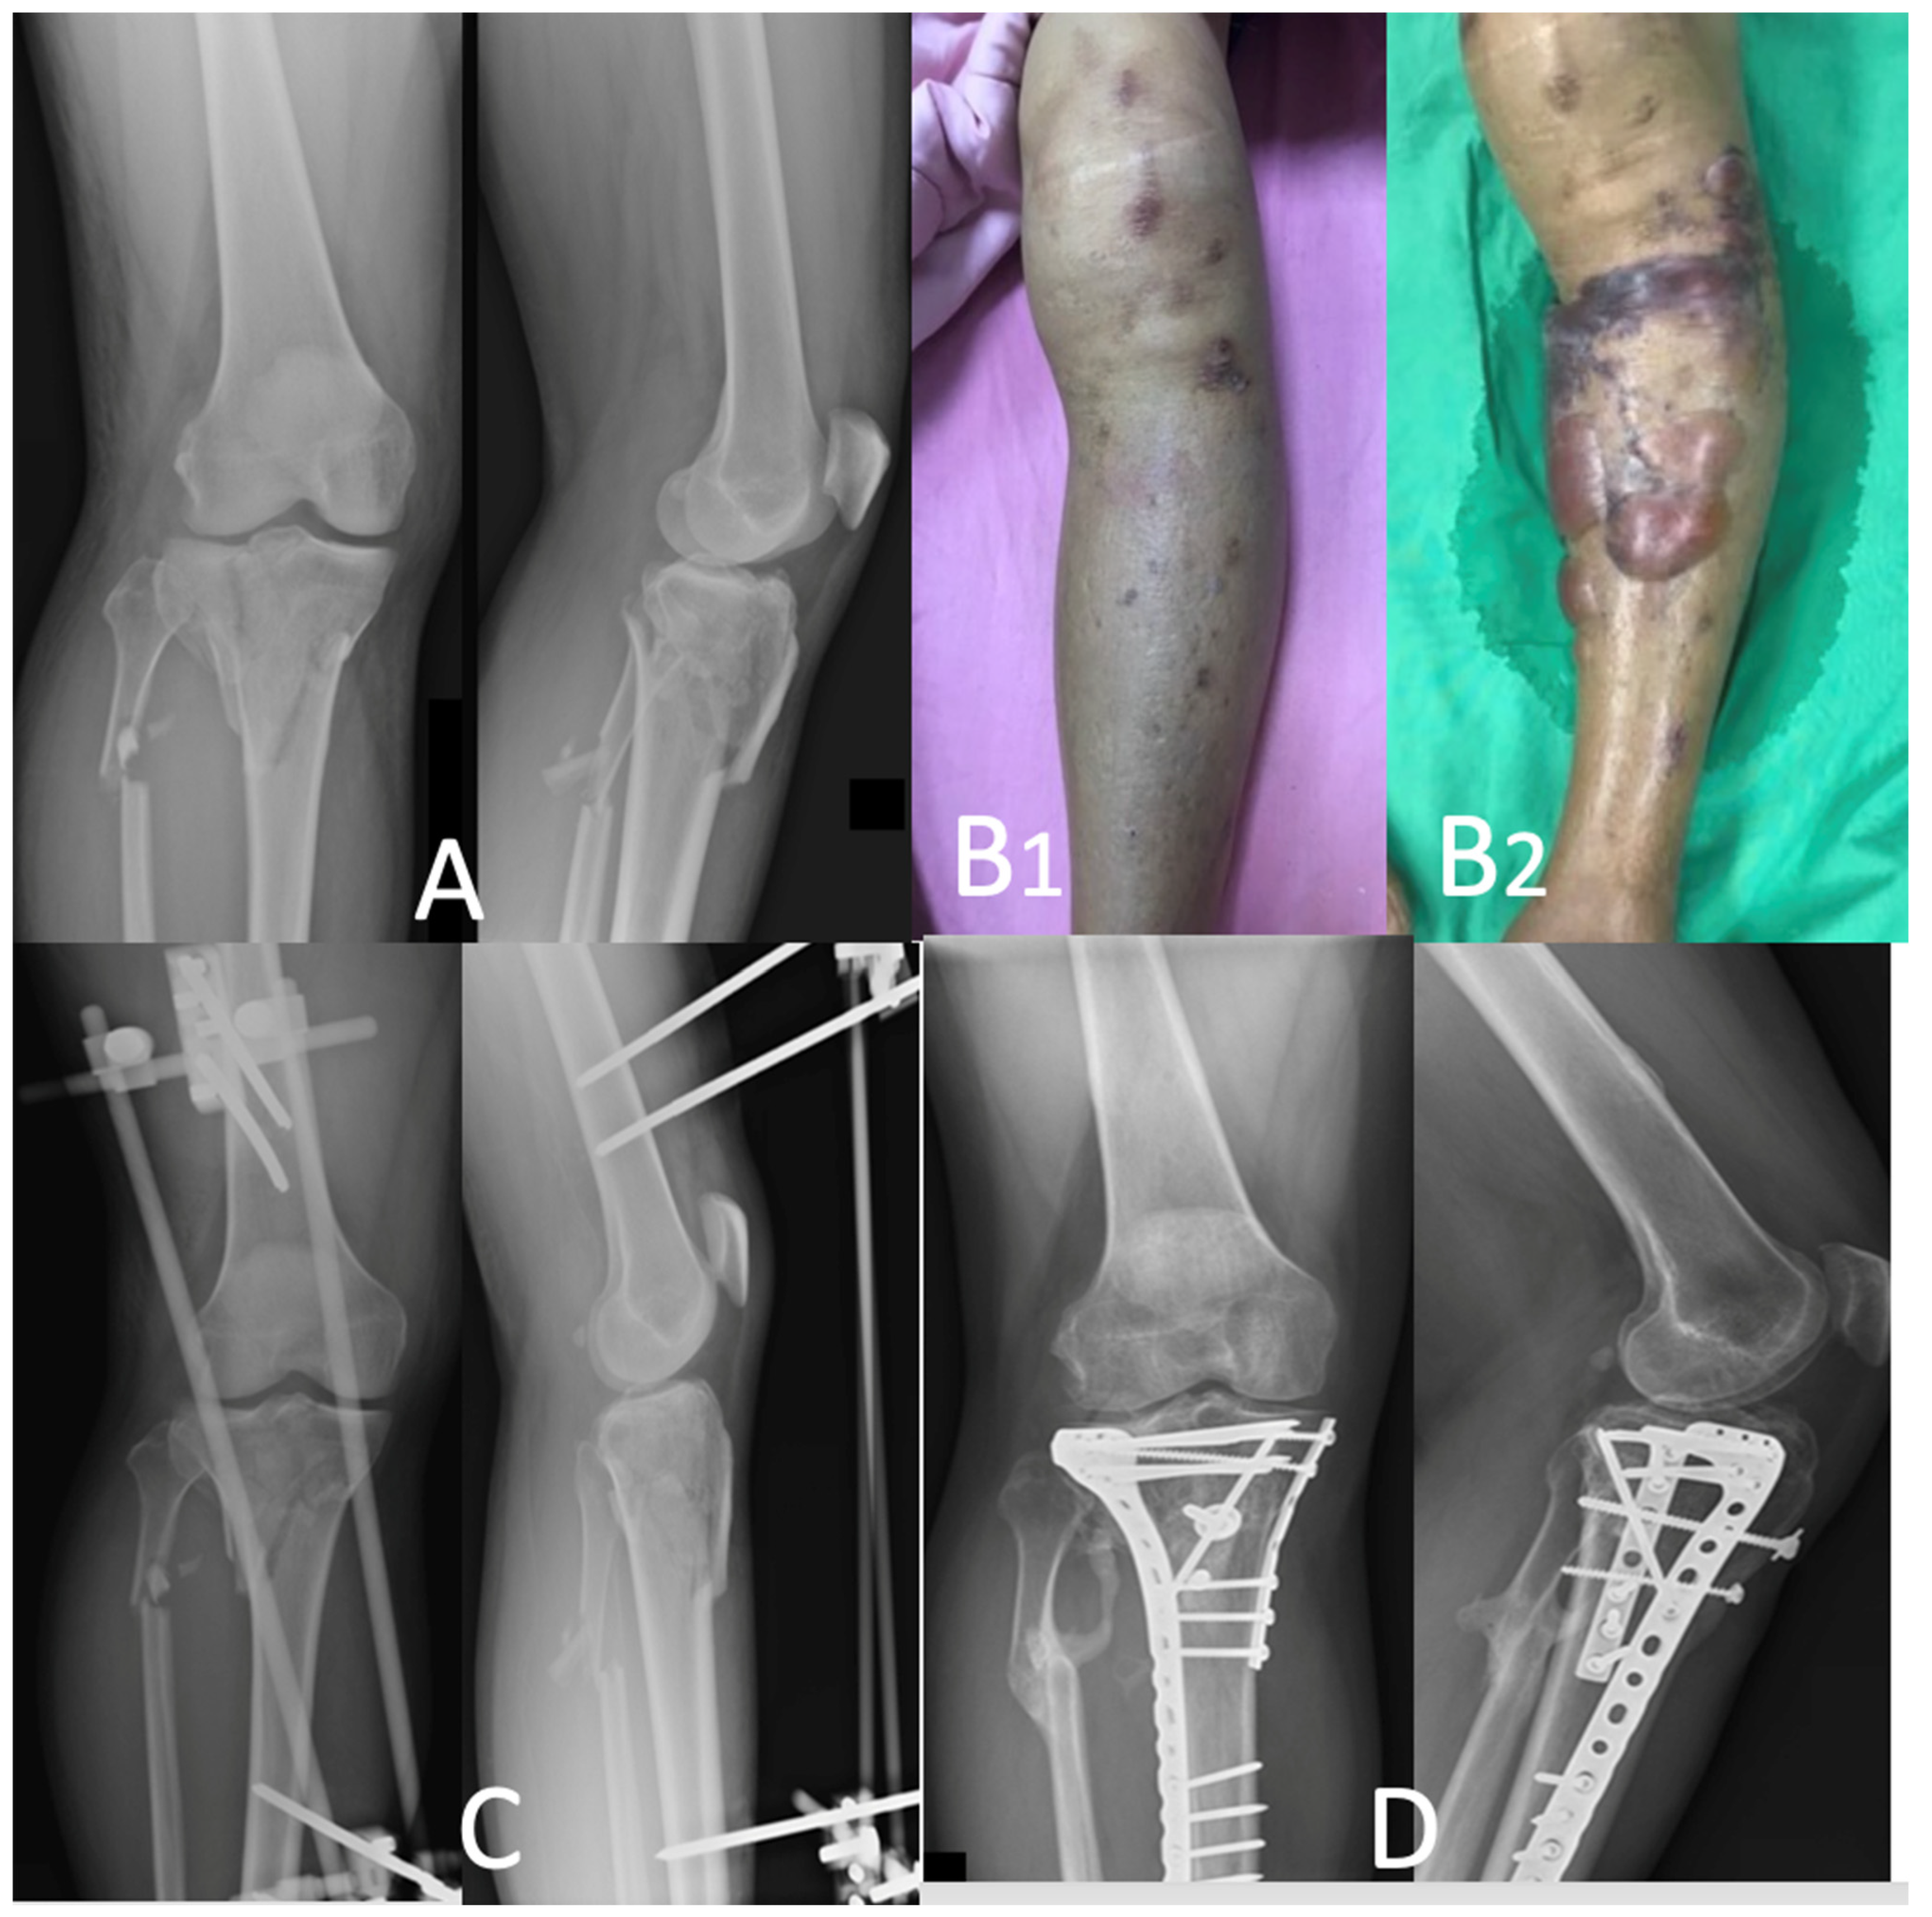

2.2. Surgical Procedures